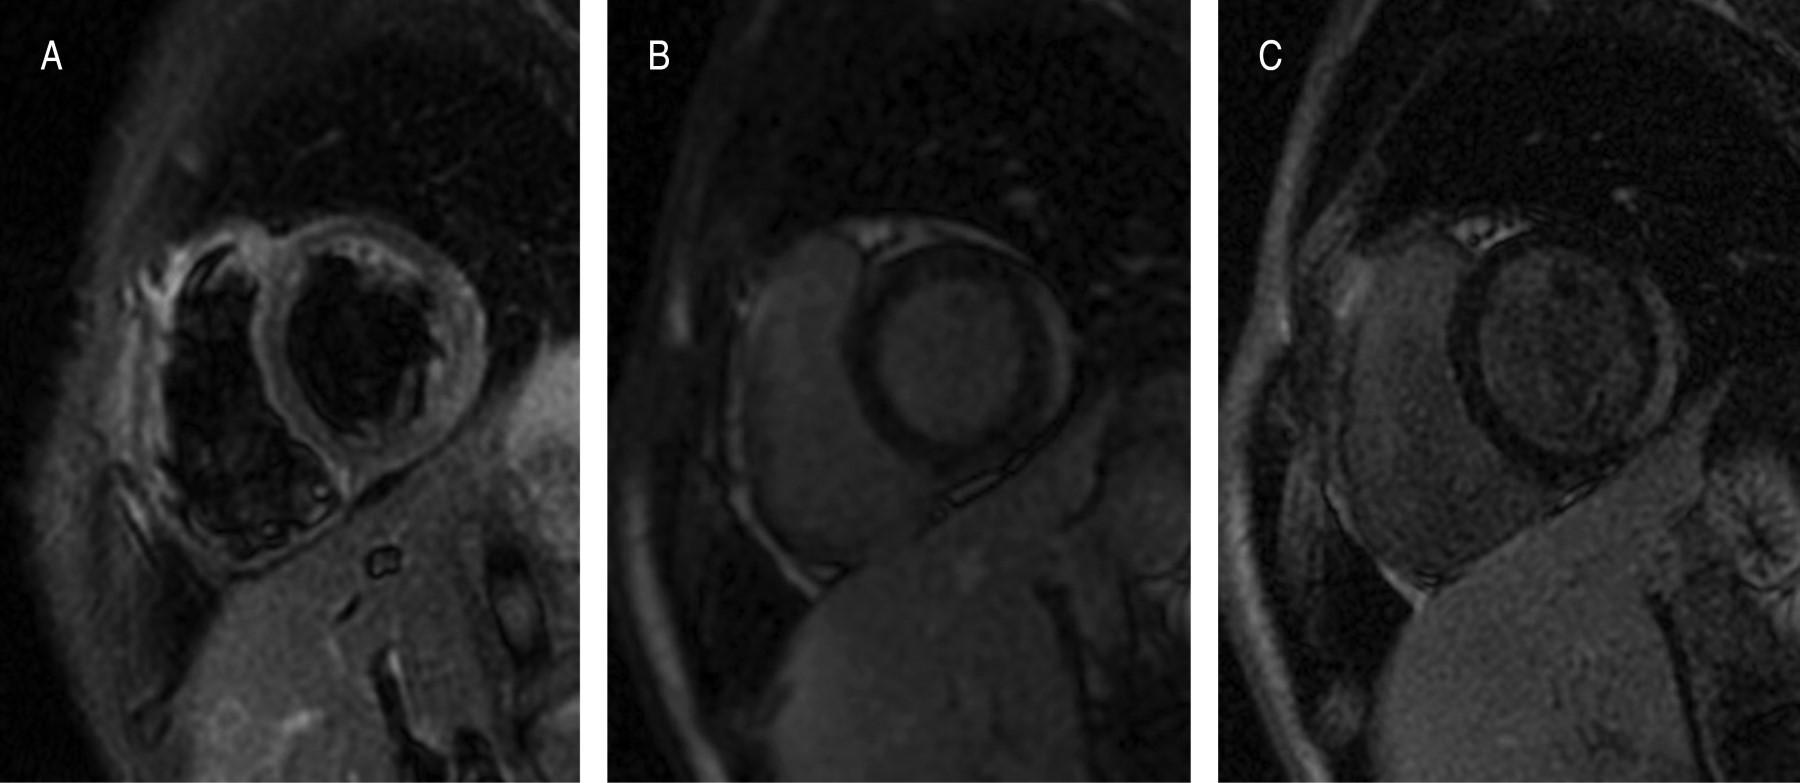

La miocarditis es una condición inflamatoria multifactorial del miocardio. La miocarditis ha sido reconocida recientemente como un evento adverso, en pacientes vacunados contra COVID-19 con Pfizer-BioNTech y Moderna (vacunas de ARNm), principalmente en adolescentes y adultos jóvenes. La resonancia magnética cardiaca (RMC) permite caracterizar el tejido miocárdico y la función cardiaca y se ha convertido en el estándar de oro no-invasivo en pacientes con sospecha de miocarditis aguda. Los autores presentan a un paciente masculino de 16 años con dolor torácico punzante tras la segunda dosis de inmunización contra el SARS-CoV-2 con la vacuna BNT162B2 (Pfizer-BioNTech). El electrocardiograma (ECG) mostró elevación del segmento ST y aumento de los biomarcadores de lesión miocárdica. La angiotomografía (AngioTC) mostró signos sutiles de hipoperfusión miocárdica y disfunción ventricular izquierda. Se realizó RMC con gadolinio, identificando hipocinesia global del ventrículo izquierdo (VI), hiperemia por edema miocárdico y realce tardío de gadolinio (RTG) como evidencia de lesión miocárdica y marcadores de lesión inflamatoria intramiocárdica no-isquémica. Habiendo excluido otras etiologías, se propone que esta presentación de miocarditis aguda sea una reacción adversa asociada a la vacuna BNT162b2 contra COVID-19. Los riesgos a largo plazo de la vacuna contra la COVID-19 en niños, adolescentes y adultos jóvenes aún se desconocen, por lo que será necesario seguir investigando.

Figura 2